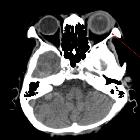

brain abscesses probably seconday to metastatic renal abscess secondary to virulent Klebsiella species. CT head shows enhanced thickened sclera on the left eye with possible adjacent abscess or inflammation.